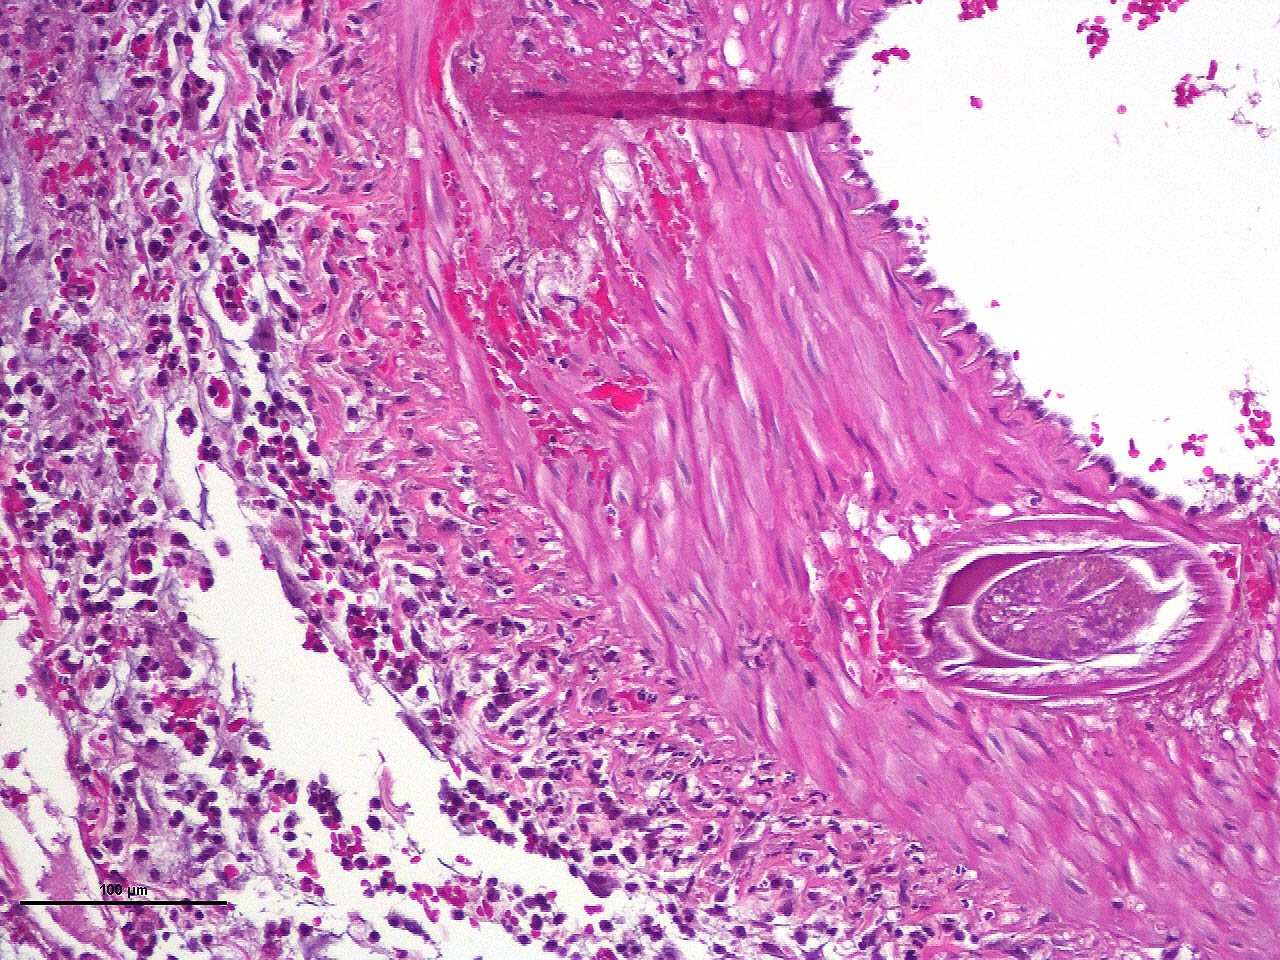

Within the media of medium to small sized arteries there were sections (not present in all slides due to the small size of the parasite – but see photomicrographs) of a nematode larva, approximately 100-200 µm in diameter with lateral allae and central digestive tract. These features are consistent with a spirurid of which Spirocerca is the most likely in our region. Foci of necrosis with hemorrhage were observed in the media of some arteries, where no larvae were identified.

Acute transmural necrotizing eosinophilic enteritis and eosinophilic peritonitis with arterial mesenteric thrombi and rare intralesional nematode larvae (spirurid)Contributor's Comment:

Aortic lesions associated with Spirocerca include intimal and medial hemorrhage and necrosis with eosinophilic inflammation, thrombus formation and rarely rupture of the aortic wall.1,2,7

- Mesentery: Arteritis and periarteritis, necrotizing and eosinophilic, chronic, multifocal, severe, with arterial thrombi and rare larval spirurids.

The JPC’s own MAJ Katie Scott moderated Conference 6 and took participants on a journey of cases from around the world; each one was from somewhere outside of the continental U.S., highlighting the truly global nature of the WSC and the importance of international contributions to pathology education. This first case provided an excellent opportunity to review of the pathogenesis and life cycle of Spirocerca lupi, both of which are well-covered in the contributor’s comment. Additionally, the lesions of spirocercosis that are considered pathognomonic in the dog were covered and include aortic scarring with aneurysms, thoracic spondylitis, and caudal esophageal nodules. Special attention was paid to the chronic arterial thrombi present in numerous arteries in this case, which are a classic part of the pathogenesis of this parasite due to its arterial migratory routes and chronic intimal irritation. Participants were also reminded of the importance of specifying what type of vessels (arteries, arterioles, veins, lymphatics, etc.) are affected when giving a description, as this can provide important clues towards pathogenesis of some diseases that may preferentially affect a specific vessel type.Spirocerca lupi is one of a handful of helminths that are classified as Group I carcinogens by the International Agency for Research on Cancer (IARC) due to the well-documented malignant transformation of S. lupi esophageal nodules into esophageal fibrosarcomas or osteosarcomas in up to 25% of infected dogs.6 Less commonly, chondrosarcomas or undifferentiated pleomorphic sarcomas can also be seen.6 Metastasis to multiple locations throughout the body, including the lungs, kidneys, stomach, spleen, heart, and tongue, occurs frequently.6,7 Significantly higher levels of interleukin-8 (IL-8) have been documented in dogs with malignant esophageal nodules.4 IL-8 is released by activated fibroblasts in pre-neoplastic nodules and is chemotactic for neutrophils. IL-8 is also involved in the tumor progression of human herpesvirus-4 (Epstein–Barr virus)-induced carcinomas.4